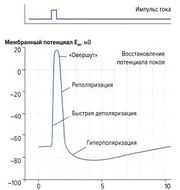

| 05:13, 20 июля 2016 | Mishci sport76.jpg (файл) |  |

9 КБ | Anes | Потенциал действия | 1 |